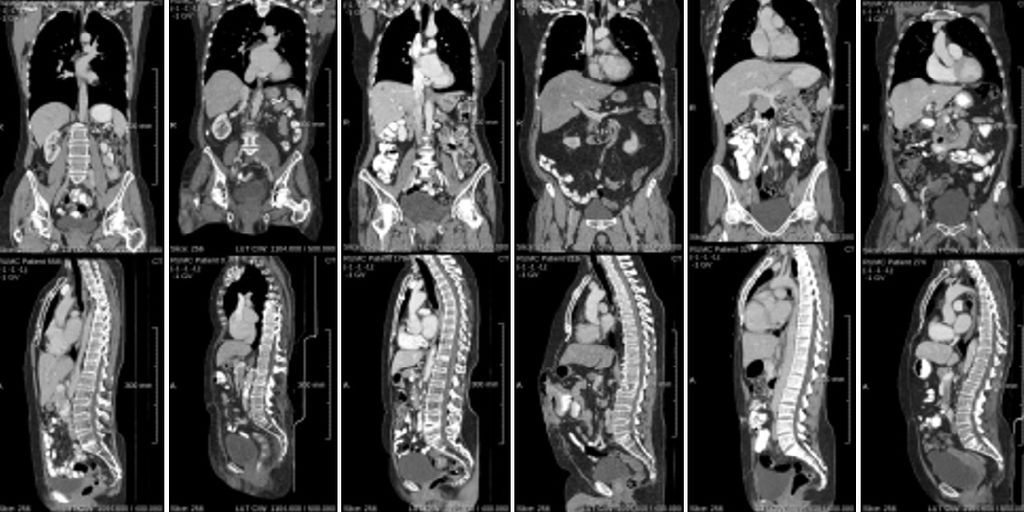

Patients with cancer metastases often have multiple CT scans taken of them over time, so that the progression of the disease can be tracked. However, manually tracking and measuring lesions is both a labor-intensive and time-consuming task. AI models may help in reducing radiologists' workload by providing assistance in longitudinal lesion tracking and follow-up diagnosis.

To effectively develop and train these AI models, human-annotated longitudinal CT scans are required. This position involves performing these annotations on a provided dataset of longitudinal CT scans. You will learn to work with the Grand Challenge platform to annotate, and gain insight into the process of tracking lesions across the whole body, among other types of annotations.